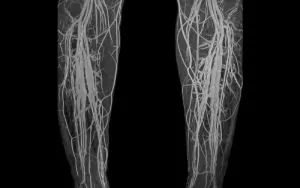

A venogram is a test that enables the doctor to see the veins in the body, especially in the legs. During the procedure, your doctor will inject a special intravenous contrast dye into the veins. The unique contrast dye makes the blood vessels appear opaque on the X-ray image. The image will provide a clear picture of the blood vessels, enabling the doctor to detect abnormalities.

Duplex ultrasound involves high-frequency sound waves to look at the speed and the direction of blood flow in the veins. This test will also show the blood vessel width and reveal any blockages. The test is less invasive, meaning that you will not experience any pain. During the test, the technician will place some gel on the skin and then press a transducer (a small handheld device) against your leg. The device emits sound waves that bounce back to a computer and shows images of how the blood is flowing through your veins.